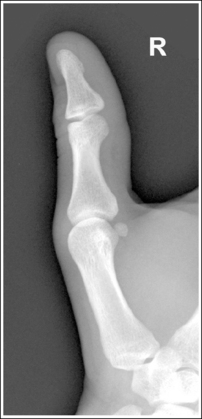

See Figures 4-12 and 4-13 and Box 4-5.

The first digit demonstrates an AP projection. The concavity on both sides of the phalangeal and metacarpal midshafts is equal, as is soft tissue width on both sides of the phalanges.

• An AP projection is accomplished by internally rotating the patient's hand until the thumb is positioned in an AP projection (Figure 4-14). The thumbnail can be used as a reference to determine when the thumb is truly placed in an AP projection. The nail should be positioned directly against the IR and should not be visible on either side of the thumb. A nonrotated AP thumb projection demonstrates equal concavity on both sides of the phalangeal and metacarpal midshafts, as well as equal soft tissue widths on both sides of the phalanges.

• Detecting thumb rotation.When the thumb is rotated away from an AP projection, the amount of midshaft concavity increases on the side of the thumb toward which the anterior surface rotates and decreases on the side toward which the posterior surface rotates. The same observation can be made about the soft tissue surrounding the phalanges when the thumb is rotated. More soft tissue width is evident on the side toward which the anterior surface is rotated, and less soft tissue width is seen on the side toward which the posterior surface is rotated (see Image 10).